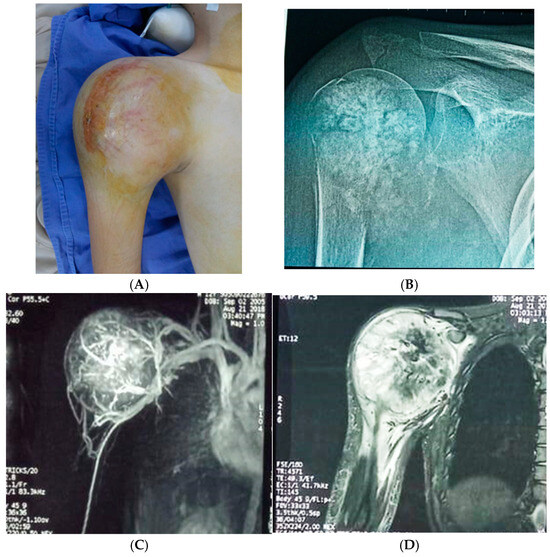

For the studied group, the main symptoms at presentation were attributed by the patient and relatives to trauma. The main symptoms were pain (93.8%), functional impotence (87.7%) and swelling (100%). Figure 2, Figure 3 and Figure 4 present the clinical, imaging and intra-operative appearance of the humeral and femoral OS for two of our patients.

Figure 2. Humeral osteosarcoma, 16-year-old male patient, 14 cm diameter tumour; (A) clinical aspect showing proximal humeral tumour, with a central scar—the site of the biopsy; (B) humeral X-ray showing periosteal destruction, infiltration in adjacent tissues and bone apposition; (C) CT scan demonstrating the rich vascularisation of the tumour; (D) MRI image with central tumour necrosis.